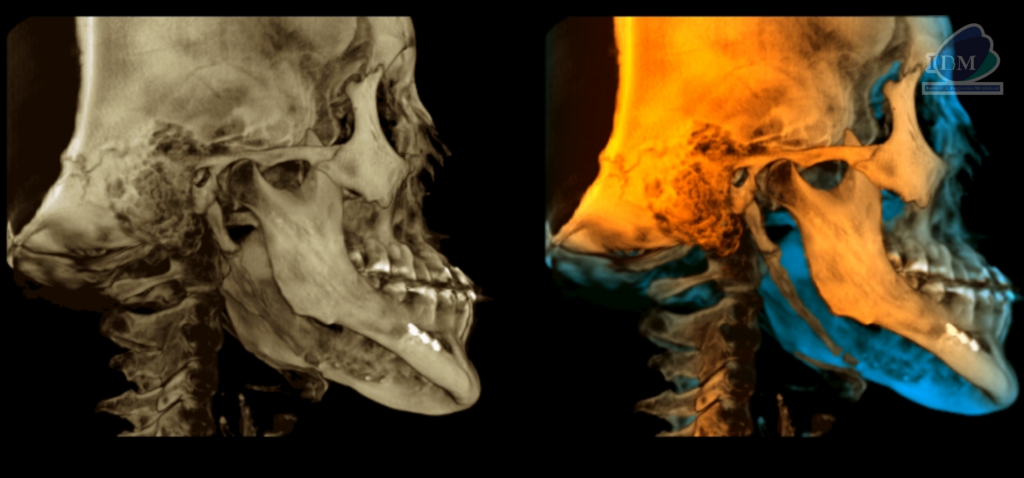

RECONSTRUCCIÓN 3D

Así mismo en la tomografía volumétrica de haz se confirma dicha mineralización, la cual se extiende desde base de cráneo hacia las astas menores del hueso hioides y presentado un patrón de mineralización pseudoarticulada.

- Mineralización bilateral de la cadena estilohioidea del tipo pseudoarticulada.